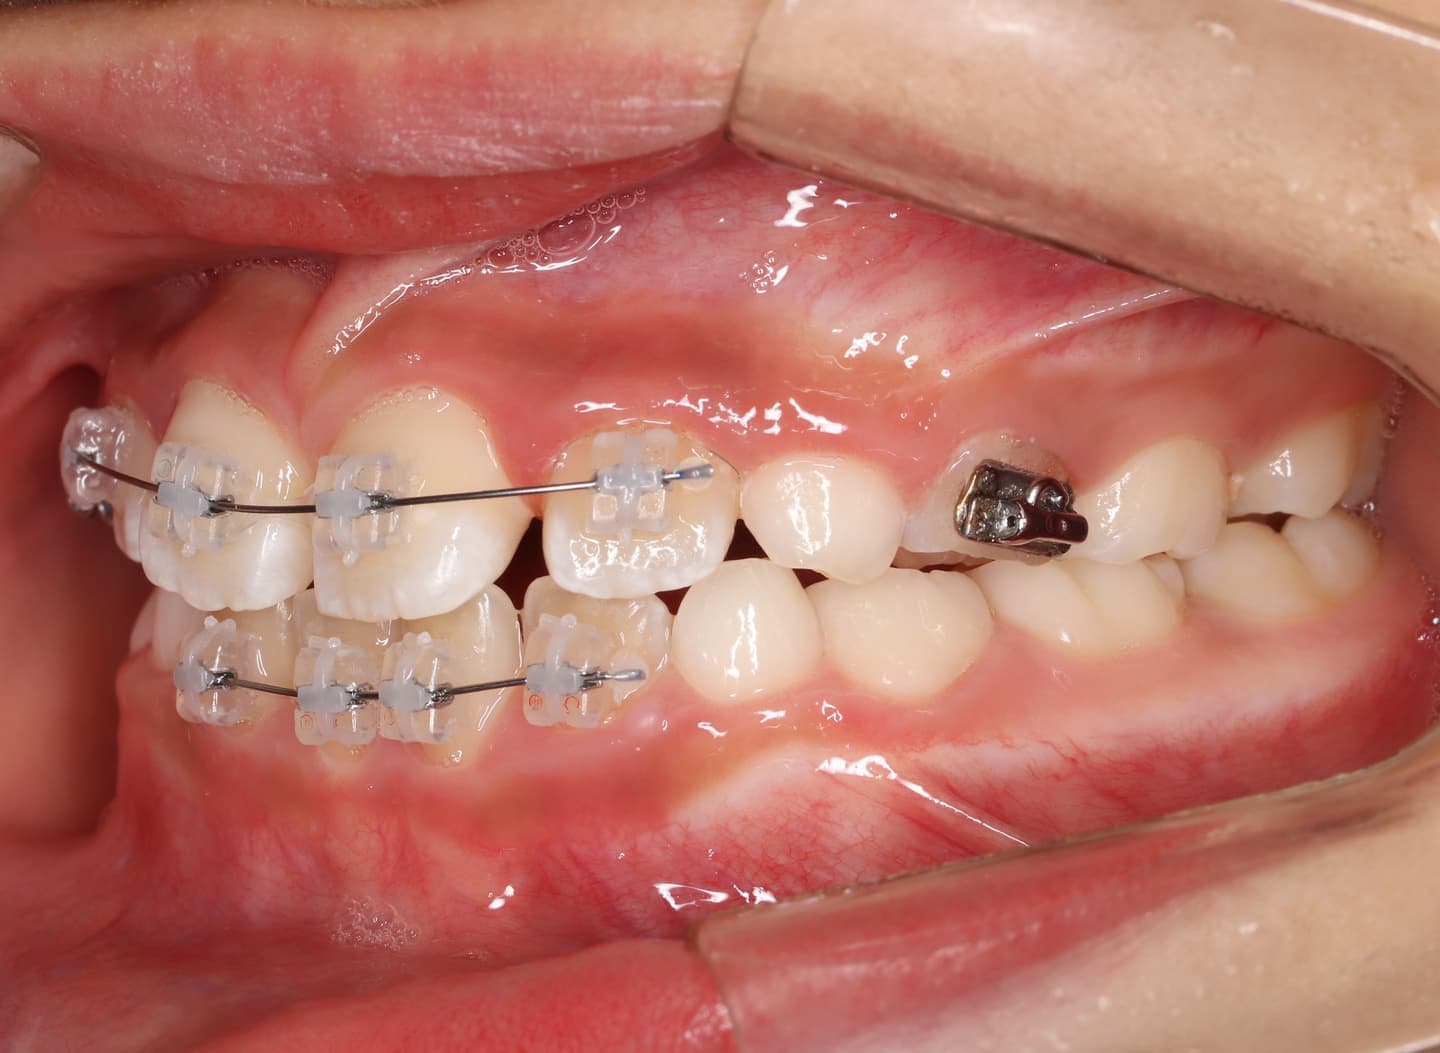

治療法:拡大プレート+フルパッシブブラケット(クリアスナップ)

治療中